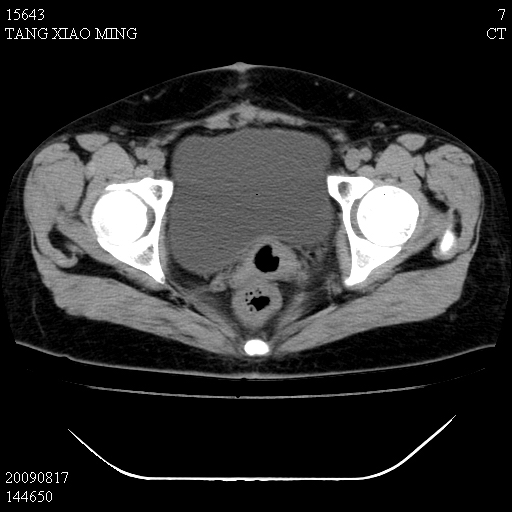

标题: CT21692:盆腔病变

女,33岁,右下腹痛2年余,既往宫外孕病史,如在我院手术,结果下周公布,

可能的诊断。1子宫内膜异位【子宫腺肌症并右卵巢巧克力囊肿】;2 右卵巢囊腺瘤。子宫肌瘤

1)考虑卵巢巧克力囊肿,不排除卵巢囊腺瘤。2)子宫肌瘤可能。

卵巢囊腺瘤,子宫肌瘤,直肠壁厚,不除外占位.